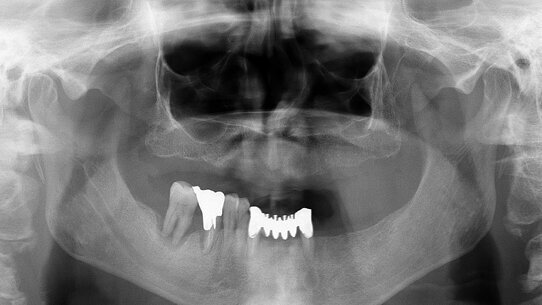

L’ortopantomografia evidenzia il mascellare superiore completamente edentulo, l’elemento dentario 4.6 caratterizzato da un’importante lesione endo-parodontale e una lesione peri-apicale a carico dell’elemento dentario 3.3 (Fig.1).

Un controllo radiografico a 10 mesi (Fig. 20) mostra una perfetta conservazione dei parametri radiologici che confermano una biointegrazione del manufatto protesico (Fig.8). I richiami periodici e la buona igiene domiciliare concorrono al mantenimento di un aspetto clinico che conforta sulla prognosi della nostra riabilitazione.